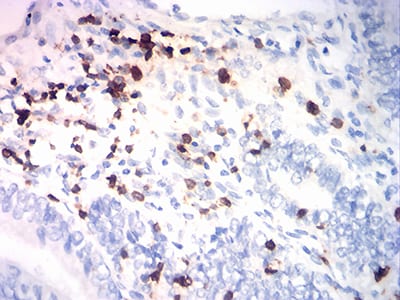

分类: 科研抗体货号: 31825别名: p150; VPS15应用: IHC,IF,FCM反应种属: Human